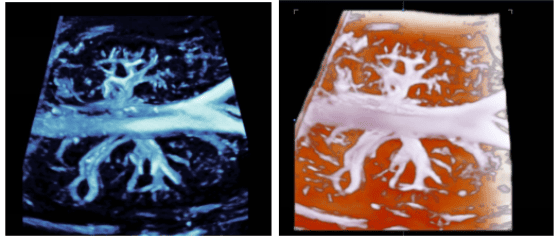

心脏组拥有多台目前世界上先进的大型彩色超声诊断仪,开展了常规心脏超声心动图、经食管超声心动图、三维超声心动图、超声引导下介入治疗和术中监测等多项检查,诊断经验丰富,技术力量雄厚。

①常规二维及三维经胸超声心动图 ②经食管三维超声心动图 ③右心声学造影(发泡试验) ④左心及心肌超声造影 ⑤胎儿三维超声心动图